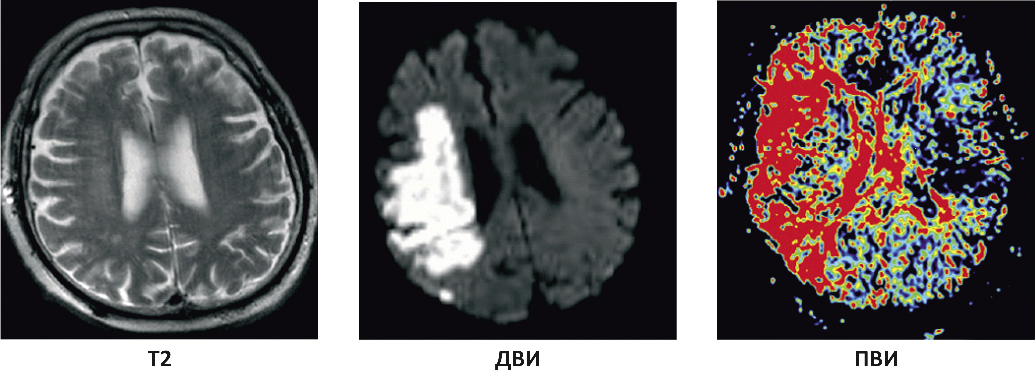

Перфузионная МРТ, как и перфузионная компьютерная томография, применяется для наиболее ранней верификации патологических изменений в веществе головного мозга и анализа степени выраженности ишемии и гипоксии при церебральном поражении: количественной оценки зон гипер- и гипоперфузии, объема мозгового кровотока и других показателей [13], в связи с чем последние годы все чаще перфузионно-взвешенные изображения становятся неотъемлемой частью диагностического протокола у больного с подозрением на церебральную ишемию (рис. 3). Следует отметить, что большая информативность перфузионной МРТ достигается при сочетании с диффузионными исследованиями, МР-ангиографией и MP-спектроскопией [1]. Диффузионная и перфузионная МРТ используются в острейшем и остром периодах ишемического инсульта для выявления изменений нейрональных структур головного мозга. Сопоставление данных, полученных с помощью обоих методов сканирования, имеет прогностическое значение, в частности позволяет дифференцировать обратимые и необратимые ишемические повреждения нейрональных структур [20], что важно для ведения больных с инсультом [12].

Рис. 3. Разные режимы МРТ головного мозга у больного с ишемическим инсультом А: Т2-изображение при стандартной МРТ – отсутствие видимых изменений вещества головного мозга; Б: ишемический очаг повышенного сигнала при диффузионно-взвешенной МРТ; В: зона гипоперфузии при карте при перфузионной МРТ превышает очаг поражения при диффузионно-взвешенной МРТ